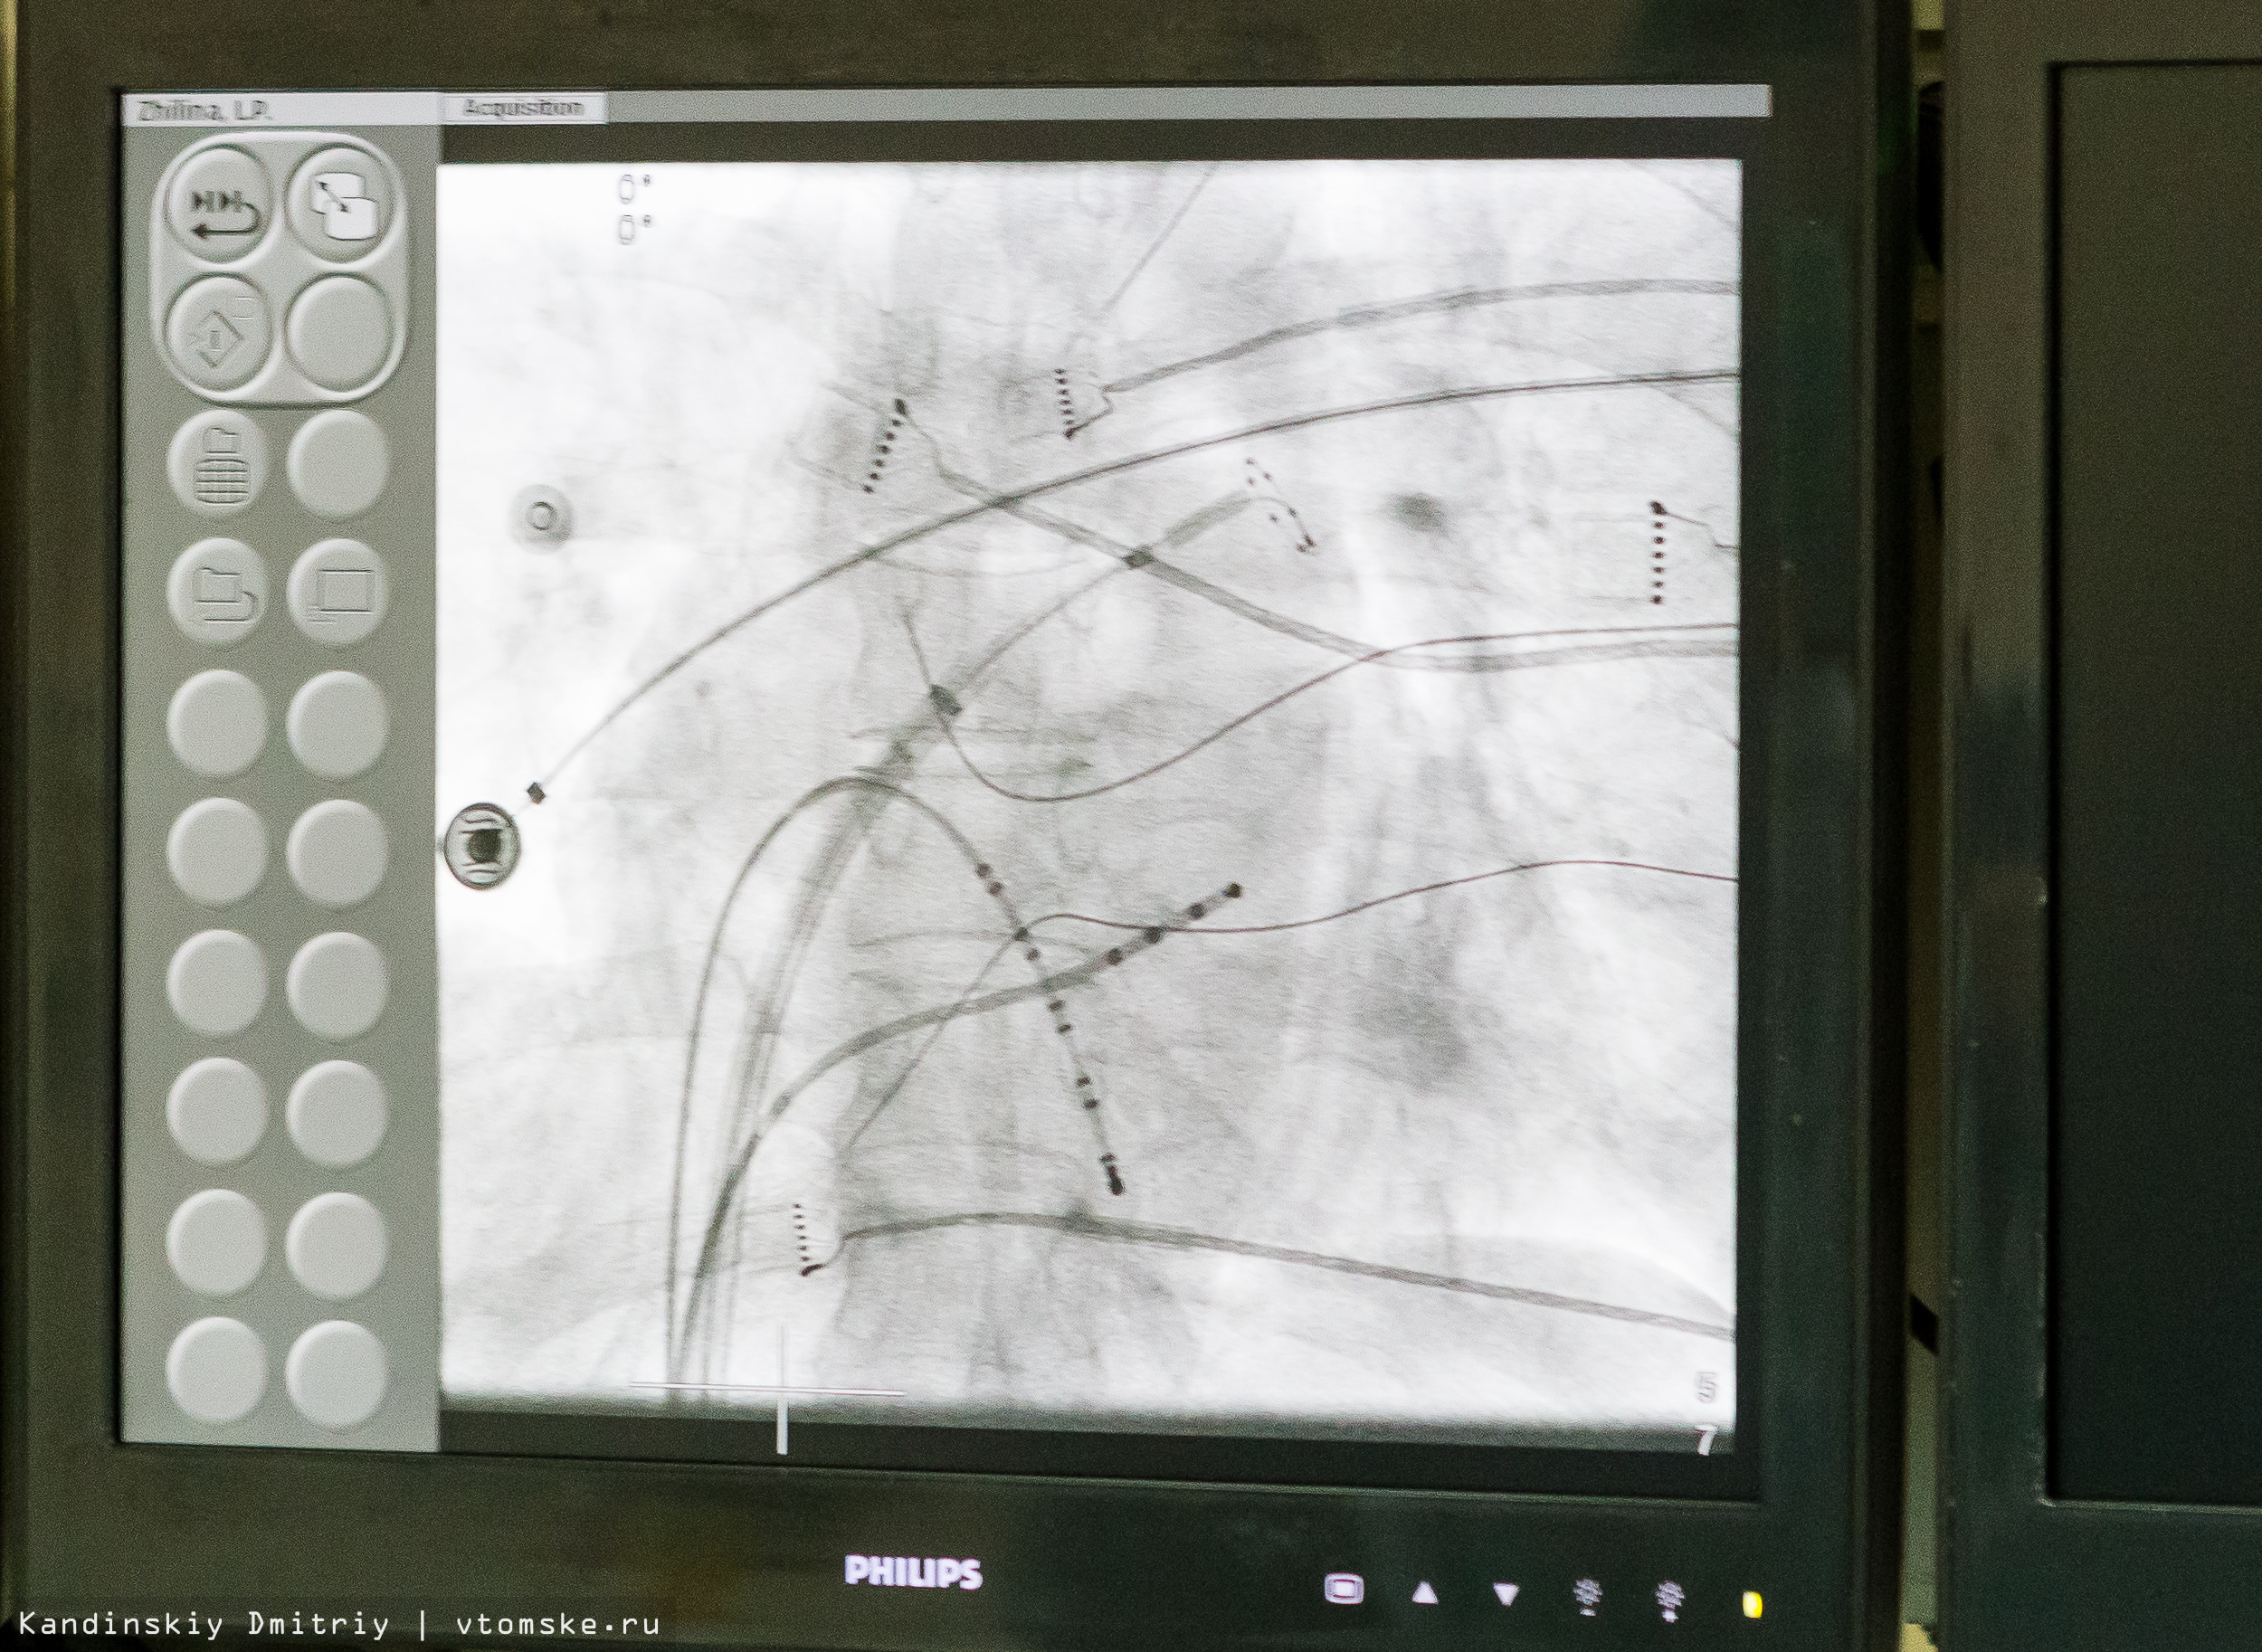

Сегодня в томском НИИ кардиологии прошла первая в России операция на сердце с использованием инновационного криобаллона, разработанного ирландской фирмой Medtronic. Операцию проводил завотделением интервенционной аритмологии Государственного научно-исследовательского центра профилактической медицины из Москвы Карапет Давтян при участии томского кардиолога Романа Баталова.

Для этого проводят пункцию бедренной вены и предсердной перегородки, через которую проводится катетер. Затем поочередно проводится контрастирование четырех легочных вен: катетер помещается в устье легочной вены, криобаллон раздувается, и подается холод. После извлечения инструмента пациенту накладывается давящая повязка, и человека помещают в палату.